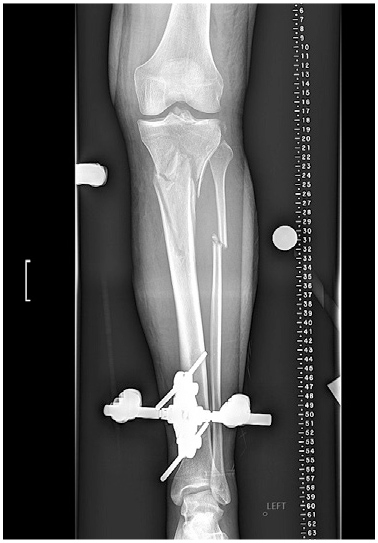

At presentation 1 week after injury, the patient was neurovascularly intact with resolving fracture blisters. The external fixator pin sites showed no evidence of infection. Radiographs showed a complex, largely extra-articular, proximal tibia fracture with dissociation of the tibial tubercle (Fig. 1). Subtle findings of a proximal lateral tibia avulsion fracture (a Segond fracture) and tibial spine comminution raised suspicion for ligamentous knee instability. Diastasis of the proximal fibula from the tibia demonstrated the high energy nature of the trauma. A computed tomography (CT) scan showed the complex proximal tibia fracture with a separate tibial tubercle fragment and confirmed a posterior cruciate ligament (PCL) avulsion fracture and lateral proximal tibia avulsion (Fig. 2). Magnetic resonance imaging (MRI) confirmed a lateral meniscal root tear, disruption of the PCL, proximal tibiofibular capsular ligaments, and moderate posterolateral corner injury (Fig. 3).

Figure 1: Anteroposterior (AP) radiograph shows spanning external fixation.